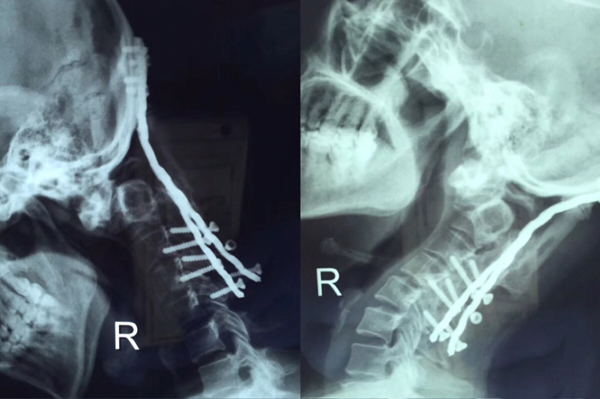

术前X线

术后X线